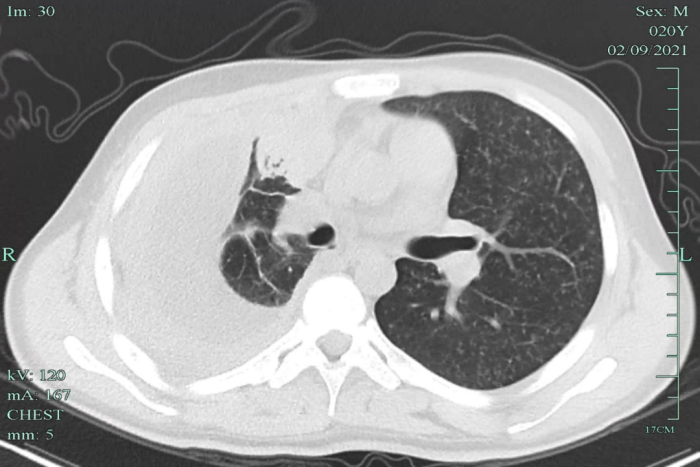

在當?shù)蒯t(yī)院檢查,發(fā)現(xiàn)小明兩肺粟粒影,提示可能血行播散性肺結核,伴有胸腔積液,提示病程比較長了,炎癥反應嚴重。小明立即來到我院感染科就診,隨后住院治療。

經全面檢查,小明被診斷為“急性血行播散性肺結核、結核性滲出性膿胸”,該類型的肺結核非常容易引起其他部位的結核播散,雖然當時小明沒有頭疼頭暈癥狀,但經過頭顱磁共振檢查發(fā)現(xiàn),其顱內有散發(fā)的結核病灶。